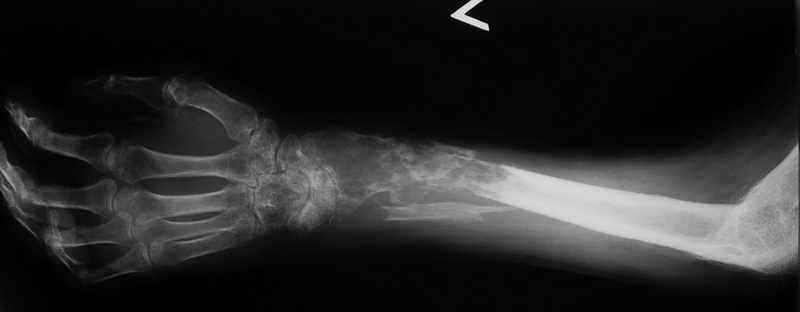

Ещё одно клиническое наблюдение - лимфома кости, до и после ПХТ и лучевой терапии.

Мамонов Василий Евгеньевич, ГНЦ РАМН